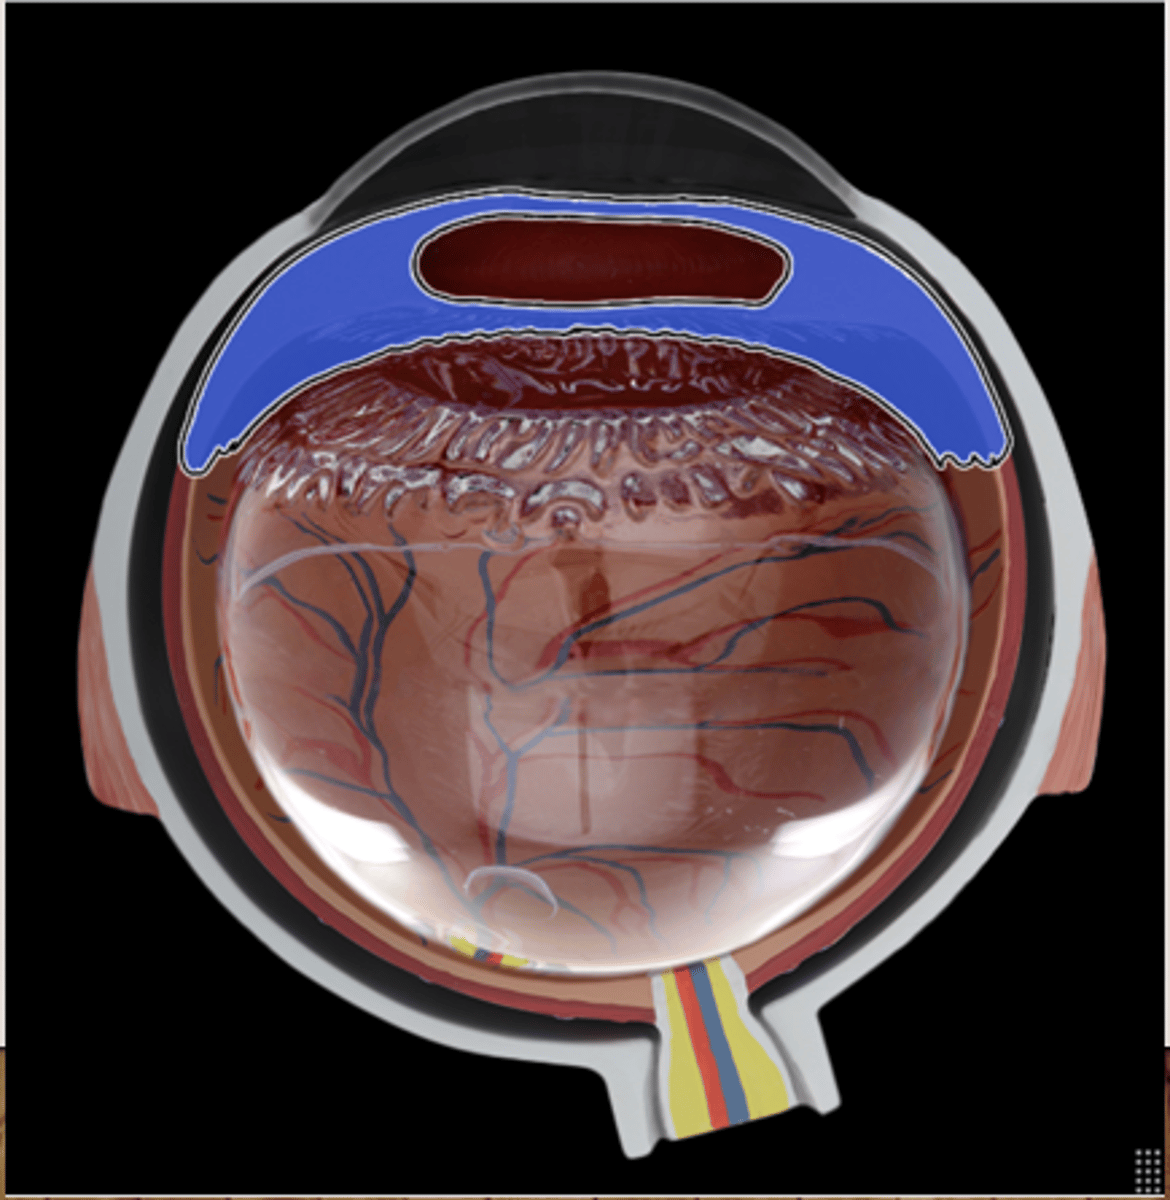

Retina

ciliary body

lens of cow`s eye

cornea

sclera

white of the eye

choroid

Iris

optic nerve

vitreous humor

soft, jelly-like material behind the lens in the viterious chamber, helps maintain shape of eyeball